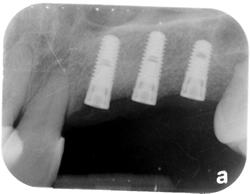

3 Implants at front:

Jan 2009

This is at front, right below the nose. In this case, there is very little room available.

3 implants are placed uneventful, right below the nasal cavity.